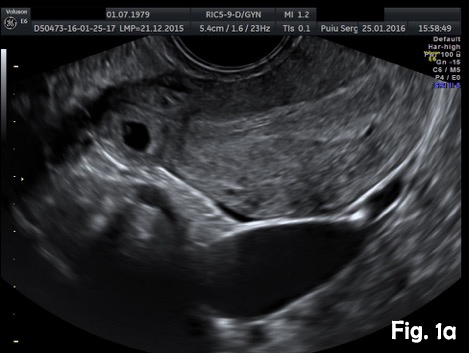

A 37-year-old woman presented for a routine dating scan at 6 weeks amenorrhea. On appointment she was asymptomatic. Transvaginal sonography revealed an empty uterine cavity and a small gestational sac with a yolk sac located eccentrically outside the endometrium, at least 5 mm from the lateral edge of the uterine cavity (Fig. 1a). A thin myometrial layer surrounding the gestational sac and an echogenic line (interstitial line) extending from endometrium to the ectopic sac was clearly seen (Fig.2b). An interstitial pregnancy was presumed. Laparotomy with excision of the interstitial pregnancy was performed. The postoperative period was uncomplicated.

Figure 1a. Transvaginal ultrasound scan, transverse view. Empty uterine cavity. A small gestational sac with a yolk sac located outside from the lateral edge of the uterine cavity.